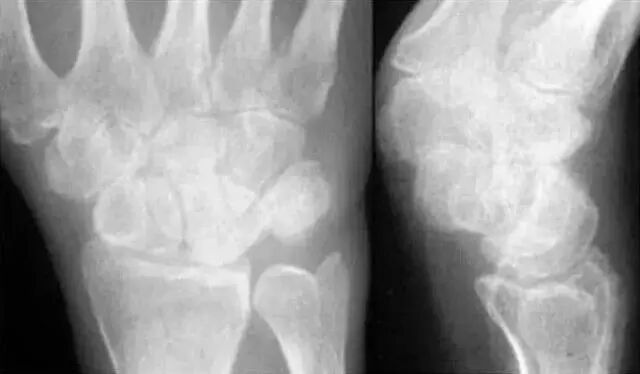

看是否有骨折:主要以舟骨、月骨常见,其他腕骨骨折一般较少,侧位注意不要漏诊三角骨即可;看桡骨远端不要漏诊关节面和纵行小梁的骨折。

两条弧线 如果不连通 多半有脱位

我们把月骨看做是香蕉,把头状骨看做是苹果。香蕉下面的桡骨关节面是盘子,盘子上面有香蕉,香蕉上放个苹果,苹果被咬了一口,在前面是三角骨骨折。香蕉歪了是月骨脱位,苹果向后是月骨周围脱位。

若显示腕骨弧线不连续或各弧线不平行,或腕掌线M形结构消失,应高度怀疑腕关节不稳或脱位。

1)月骨脱位:正位片示月骨由四边形便成三角形或橘瓣状,并向尺侧移位。侧位月骨前移、旋转,窝状关节前空虚。

2)经舟骨月骨脱位:除月骨脱位外,同时伴有周骨骨折,且骨折近段随月骨一起向前脱位,骨折远端仍处于原位置。

3)月骨周围脱位:表现为腕关节缩短,头骨与桡骨距离变近,头骨、钩骨与月骨部分重叠,月骨形态及位置基本正常。

4)经舟骨月骨周围脱位:表现为月骨周围脱位拌周骨骨折,且骨折远端随头骨向后脱位,而骨折近段与桡骨、月骨关系保持正常。

5)混合型脱位:月骨周围脱位,月骨也有半脱位。甚至有腕骨骨折、尺桡骨骨折、尺桡下关节脱位等。

• 正位片上,前后排腕骨后缘形成光滑的弧线:前后排腕骨不重叠:头、钩、月三角骨间形成十字间隙。

• 月骨于正位片上为楔形、侧位片上为月牙形,窝状关节面朝前、且与头状骨紧贴。

• 侧位片上,桡骨纵轴通过月骨和头骨;前排腕骨自下而上分别为大、小、头、钩骨,后排自下而上为舟、月(豆)、三角骨。